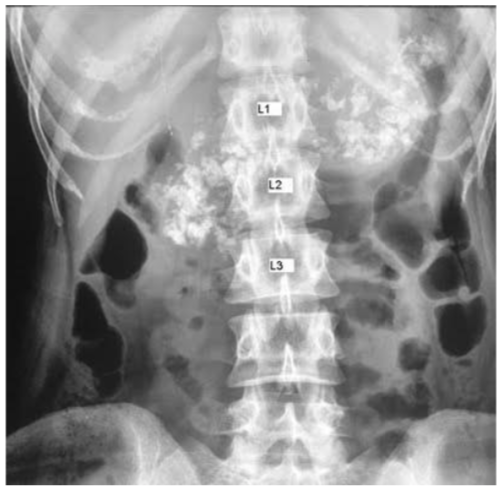

A 51-year-old man complains of passing foul-smelling fatty stools. He noticed recent loss of weight as well; an abdominal x-ray was performed, and findings can be observed as below. How would u manage this patient?

By supplementing him with pancreatic enzymes